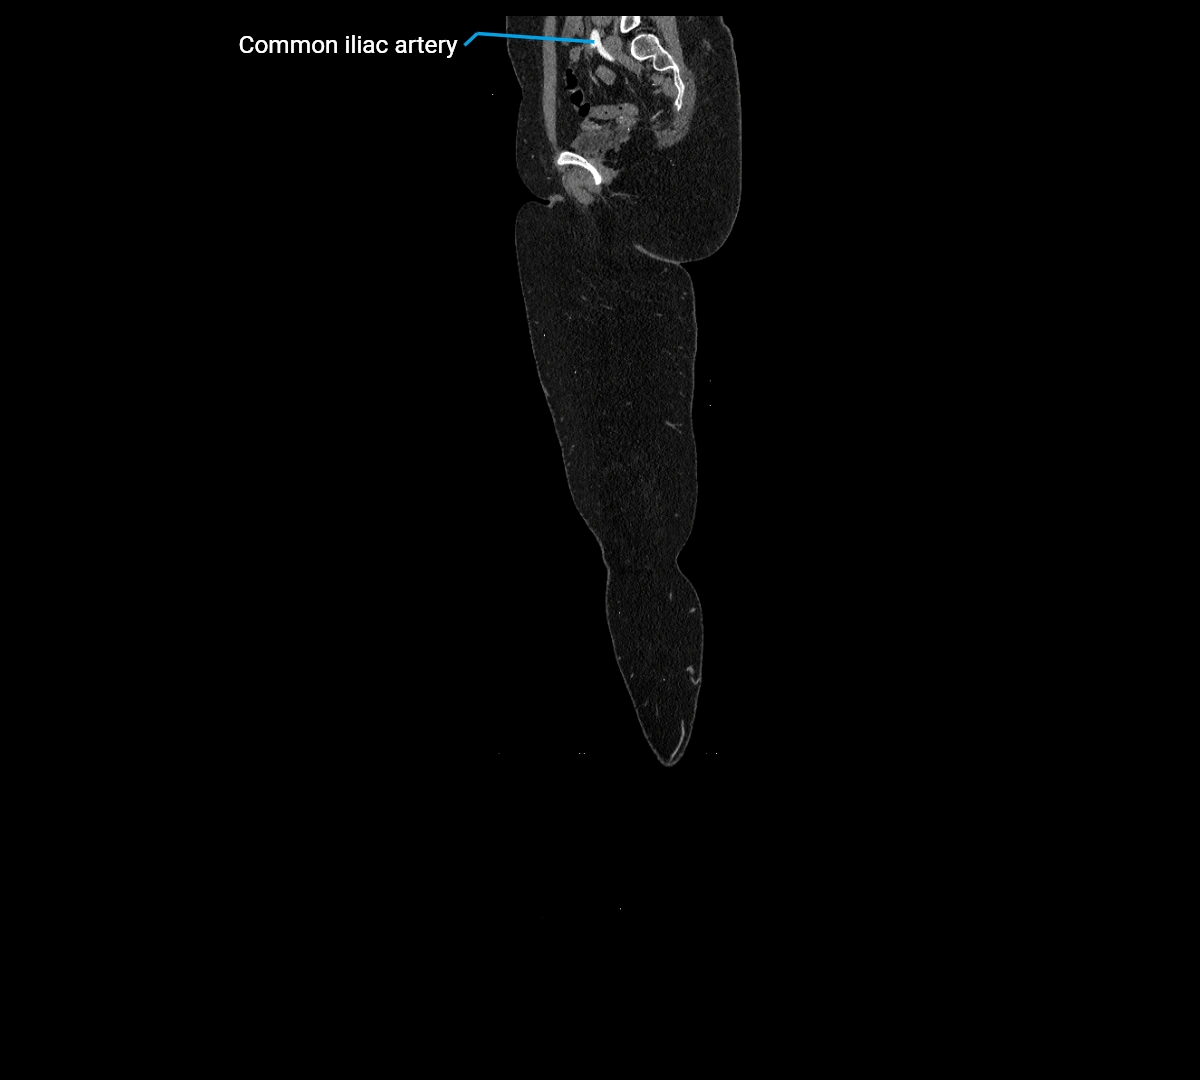

CT images

image

Contrast-enhanced CT (CTA):

• Gold standard for abdominal aortic imaging

• Provides excellent detail of lumen, wall, aneurysm, thrombus, and branch vessels

• Multiplanar and 3D reconstructions help in aneurysm measurement, stent graft planning, and dissection evaluation

• Detects acute rupture, traumatic injury, or occlusion with high sensitivity